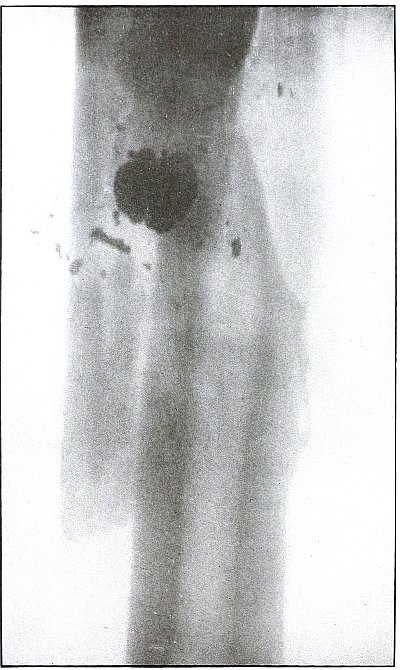

52. Gunshot fracture, femur 114

53. Gunshot fracture, femur 116

54. Gunshot fracture, femur 118

55. Gunshot fracture, femur 120

56. Gunshot fracture, femur 122

57. Gunshot fracture, femur 124

58. Gunshot fracture, femur 126